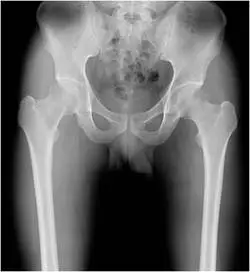

23歲男性無特殊病史,近二個月來,他覺得舉重物時右髖部附近會痛,附圖為 X 光攝影,最可能的診斷為何?

從骨盆與雙側股骨正位攝影可見:

- 右側近端股骨(包含股骨頸及大轉子區域)呈現管狀骨皮質向外擴張,皮質變薄但仍完整,未見明顯破壞性骨質缺損或侵蝕。

- 病灶區域呈均質半透亮(hazy lucency),內部類似「ground-glass」樣雲霧狀骨基質,並可見周邊略帶增生性硬化(rind sign)。

- 無明顯骨膜反應(如 sunburst 或 Codman 三角),也無明顯軟組織腫塊或周圍水腫。

- 病灶位置偏向長骨幹端(metaphysis/diaphysis),非純粹骨骺端病變。

這些特徵符合 monostotic fibrous dysplasia,在近端股骨最為常見。(theamericanchiropractor.com)